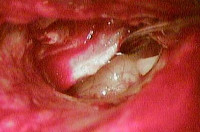

Особенности операции при хроническом гнойном среднем отитеМожно выделить три приоритета в лечении хронического гнойного среднего отита: 1) устранение заболевания, 2) профилактику рецидива заболевания 3) сохранение или восстановление слуха. Именно поэтому выбор хирургической тактики основывается на длительности заболевания, общем состоянии пациента, состоянии противоположного уха, опыте хирурга и предпочтениях пациента. Мастоидэктомия при хроническом гнойном среднем отите имеет три первичных показания: устранение воспаления и инфекционного процесса, доступ для удаления холестеатомы, и, что не менее важно, создание аэрации. Некоторые хирурги считают, что неудачные предыдущие тимпанопластики и персистирующее гноетечение из уха являются показанием к мастоидэктомии, но в большинстве случаев эти состояния могут быть устранены только правильно выполненной тимпанопластикой. Небольшие, изолированные от барабанной перепонки холестеатомы или маленькие врожденные холестеатомы также могут полностью излечиваться без мастоидэктомии. Дискуссионным является выбор сохранения или удаления задней стенки слухового канала, т.е. открытой (CWU) или закрытой (CWD) мастоидэктомии. При CWD мастоидэктомии задняя стенка наружного слухового прохода удаляется для расширения доступа к среднему уху и эпитимпануму и для выведения любой неоперабельной матрицы холестеатомы, например, холестеатомного матрикса, прикрывающего фистулу латерального полукружного канала. Открытая мастоидальная полость, образованная в результате CWD хирургии, эпителизируется в течение нескольких последующих месяцев и требует частых амбулаторных осмотров для ухода за полостью, особенно на начальном этапе. Даже при полном заживлении необходим уход и пожизненное наблюдение за полостью. Увеличение объема хирургического вмешательства с удалением стенки наружного слухового прохода, как сообщается, приводит к снижению темпа роста и процента рецидивов заболевания по сравнению с CWU мастоидэктомией. В других сообщениях указывается, что на темпы роста холестеатомы и частоту возникновения рецидива не влияет удаление стенки наружного слухового прохода, тогда как на частоте рецидивов существенным образом сказываются особенности расположения холестеатомы. Кроме того, расширенный слуховой проход менее эстетически привлекателен, из-за чего больные могут испытывать стеснение. Сохранение задней стенки наружного слухового прохода также положительным образом сказывается на сокращении послеоперационного периода, реже возникает необходимость ухода за послеоперационной раной в амбулаторных условиях. Сохранение стенки наружного слухового прохода позволяет избежать ограничения попадания воды и предполагает больший выбор слуховых аппаратов по сравнению с трудностями при ношения в открытой полости. Традиционно считается, результаты слуховой функции лучше при CWU по сравнению с CWD мастоидэктомией. На самом деле, в большей степени это связано с особенностями патологического процесса, вызвавшего необходимость операции, чем с наличием или отсутствием стенки наружного слухового прохода. Другие авторы отмечают, что между этими вариантами операций нет существенных различий слуховой функции, и более важна степень эрозии слуховых косточек. Обычно после CWU мастоидэтомии через 6-12 месяцев назначается второй этап оперативного лечения, включающий оценку наличия рецидива и реконструкцию цепи слуховых косточек. Сторонники же CWD мастоидэктомии не видят необходимости в выполнении второго этапа операции. Сохранение стенки наружного слухового прохода в нашей практике предпочтительнее. Решение об удалении стенки наружного слухового прохода принимается во время операции, когда в полной мере можно оценить объем патологического процесса. Интраоперационные данные, определяющие выполнение CWD мастоидэктомии следующие: фистула лабиринта, неоперабельное заболевание лицевого нерва или подножной пластинки стремени, низкое расположение крыши аттика, затрудняющее подход к нему, неоперабельное заболевание барабанного синуса и нереконструируемый дефект задней стенки наружного слухового прохода. Удаление стенки наружного слухового прохода не облегчает подхода к барабанному синусу. Наши предоперационные исследования редко приводят к решению удаления задней стенки. Очевидное разрушение задней стенки наружного слухового прохода или фистула лабиринта на КТ у пожилых или ослабленных пациентов, у которых выполнение плановой хирургической ревизии нецелесообразно, особенно при одном слышащем ухе — это состояния, при которых единственно возможным вариантом лечения будет CWD. Возможность выполнения CWD мастоидэктомии обсуждается с пациентом до операции при получении информированного согласия, причем всегда необходимо оговаривать, что во время операции может возникнуть необходимость удаления задней стенки наружного слухового прохода. Хронический средний отит с холестеатомой: а, б — Краевой дефект в переднем верхнем квадранте барабанной перепонки, в, г — Крупная краевая перфорация в верхнем заднем квадранте. Хронический воспалительный процесс разрушил стенку слуховой трубы в задневерхней ее части. Особенности мастоидэктомии у детей с холестеатомойОбщеизвестный (но спорный) факт, что у детей холестеатома имеет более агрессивный характер. В то время как незрелая слуховая труба может способствовать втяжению барабанной перепонки и образованию холестеатомы, есть предположения, что большое количество факторов роста у детей способствует ускоренному росту холестеатомы. Кроме, того дети с хроническим гнойным средним отитом имеют лучшую аэрацию сосцевидного отростка, чем взрослые, что может способствовать распространению холестеатомы через барабанную полость в сосцевидный отросток и затрудняет ее полное удаление. Несмотря на эти общепринятые представления, лишь одно исследование показало какую-либо молекулярную разницу между взрослой и детской холестеатомой. Bujia et al. продемонстрировали быструю скорость репликации кератиноцитов в детской холестеатоме по сравнению со взрослой. Число рецидивов после хирургического лечения холестеатомы у детей, по данным литературных источников варьирует от 5 до 71%. В одном сравнительном исследовании 66 пациентов Dodson et al. проанализировали свой опыт и обнаружили, что общий рецидив (текущий и остаточный) болезни при CWU мастэктомии в детском возрасте составил 42% против 12% у взрослых пациентов. Только у 17% пациентов потребовалось увеличение объема вмешательства при CWU мастоидэктомии при возникновении рецидива до CWD мастоидэктомии (средний период наблюдения 37,6 месяцев). Несмотря на разницу в наличии рецидивов, авторы настаивают на проведении CWU мастоидотомии и обосновывают это меньшими проблемами, связанными с образованием послеоперационной полости. Слуховая функция в обеих группах была схожа. Большое количество рецидивов после CWU мастоидэктомии в педиатрической практике свидетельствует о том, что операцией выбора в педиатрической практике является CWD мастоидэктомия. CWD мастоидэктомия не гарантирует возникновения рецидива холестеатомы, как было показано в исследованиях Shirazi et al., которые представили работу по анализу 166 случаев холестеатомы (как приобретенной, так и врожденной) в педиатрической практике со средним сроком наблюдения шесть лет. В 8% случаев после CWU мастоидэктомии потребовалась ревизионная операция по поводу рецидива заболевания, тогда как после CWD мастоидэктомии повторная операция потребовалась у 21% больных. Интересно, что после CWD лишь в 28% случаев операция выполнялась в связи с рецидивом заболевания, остальные 72% вмешательств были выполнены из-за стеноза и гранулирования. В целом, частота рецидивов после CWU и CWD составляет 8% против 6%, что не является статистически значимым. Как и другие авторы, они установили, что состояние стенки наружного слухового прохода не сказывается на послеоперационном состоянии слуха, скорее на послеоперационный результат влияет степень эрозии стремени. Как и во взрослой, в педиатрической практике, мы стараемся по возможности сохранять заднюю стенку наружного слухового прохода. Решение об удалении задней стенки принимается интраоперационно. Задняя стенка удаляется при наличии фистулы полукружного канала или при значительном ее разрушении. Разрушения латеральной стенки аттика реконструируются хрящом, что предотвращает образование ретракционных карманов. В тяжелых случаях барабанная перепонка на всем протяжении уплотняется хрящом. Мы не наблюдали случаев снижения порогов слуха после такого вида укрепления. Через 12 месяцев пациентам выполнялась вторая операция и реконструкция цепи слуховых косточек. Решение о необходимости второго этапа принимается во время первой операции. Во время первой операции тщательно обозначается размер и локализация патологического процесса. Часто второй этап и реконструкция слуховых косточек проводятся через эндоуральный доступ, осматриваются основные места возникновения рецидивов: стремя, лицевой нерв, тимпанальный синус. Заушный доступ выполняется при выявлении на первом этапе вовлечения твердой мозговой оболочки или плохой визуализации аттика. Мы убеждены, что сохранение задней стенки наружного слухового прохода очень важно в детском возрасте, будь то изначальное сохранение или восстановление. На самом деле мы предпочитаем выполнить и третью ревизионную операцию для контроля заболевания, при подозрениях на образование открытой полости. Противопоказания к мастоидэктомии при хроническом среднем отитеПротивопоказания к выполнению CWU мастоидэктомии включают: нереконструируемый дефект задней стенки наружного слухового прохода, случаи, когда выполнение процедуры в полном объеме под вопросом, а также неоперабельную матрицу холестеатомы, поражающую лабиринт, лицевой нерв, сонную артерию, мозговую оболочку, и барабанный синус. Активная инфекция и выделения не являются противопоказанием к операции, но необходимо провести лечение и сделать ухо как можно более сухим. Частота послеоперационных инфекций выше, если ухо во время операции не сухое. Предоперационное ведение и планированиеКак обсуждалось ранее, тщательный сбор анамнеза и полное обследование головы и шеи с бинокулярной отомикроскопией важны, если это возможно сделать при первичном осмотре. У пациентов, которым консервативная терапия не проводилась, а также при выявлении холестеатомы обсуждается возможность выполнения операции. КТ выполняется обычно не всем пациентам. Это исследование необходимо для детальной оценки анатомии и установления диагноза у больных с головокружением, параличом лицевого нерва, болью или другими симптомами, указывающими на осложнения. Ревизионная операция также является показанием для КТ, особенно если предыдущая операция была выполнена не в нашей клинике. — Также рекомендуем «Техника мастоидэктомии с сохранением стенки наружного слухового прохода (CWUM, canal-wall-up mastoidectomy)» Оглавление темы «Мастоидэктомия с сохранением стенки наружного слухового прохода.»: